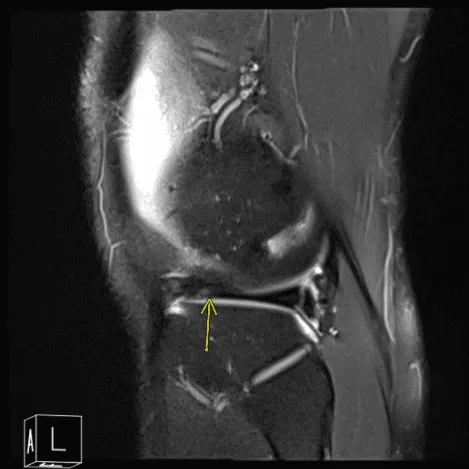

Tras una semana, los resultados de la resonancia magnética recibidos y comentados con el paciente mostraron que, además del derrame articular, se observan algunos cambios degenerativos en el compartimento patelofemoral y en la parte posterior de la meseta tibial medial, que podrían estar relacionados con el SNP focal.

Resonancia magnética de rodilla izquierda